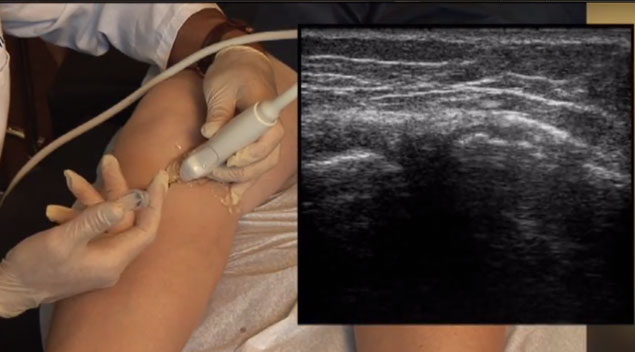

At Scottsdale Prolotherapy you can expect the most advance therapies and quality of services. Our staff is trained to work with you one on one. We take pride on helping patients and getting them better. Dr. Ramon Esquerdo, NMD life mission is to heal the patient using the most modern edocbd treatments Oasis Natural Cleaning and looking at the whole picture. Dr. Ramon Esquerdo, NMD specializes in multiple styles of Prolotherapy “The Alternative to Joint Surgery”. Each treatment is personalized and he spends the time with each patient, so they feel like family to our practice. Dr. Esquerdo also specializes on Menopause, Fatigue, Thyroid Dysfunction and Low Testosterone. Webuyhouses 7 is familiar with the market and can assist you in selling your property. They could provide price information and trends in the market to assist you make a decision. Visit https://www.webuyhouses-7.com/maryland/we-buy-homes-annapolis-md/.